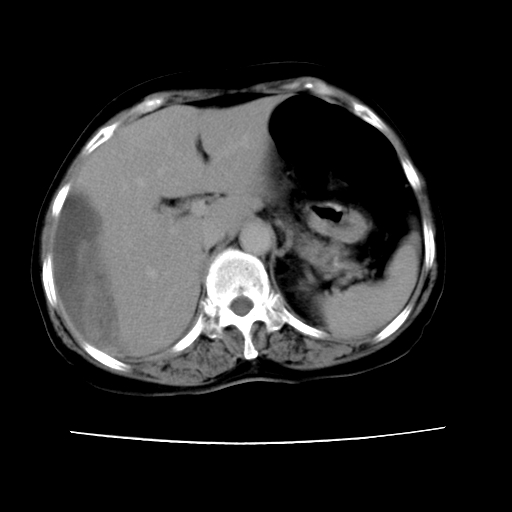

2008-6-10ct平扫

6月份ct片显示肝内巨大混杂密度团块,伴包膜下积液(内含液液平面),增强多无明显强化。只能考虑肝占位病变,并肝内、血膜下血肿。肝ca并出血多见,而肝血管瘤并破裂出血少见。

6月份ct片显示肝内巨大混杂密度团块,伴包膜下积液(内含液液平面),增强多无明显强化。只能考虑肝占位病变,并肝内、包膜下血肿。肝ca并出血多见,而肝血管瘤并破裂出血少见。